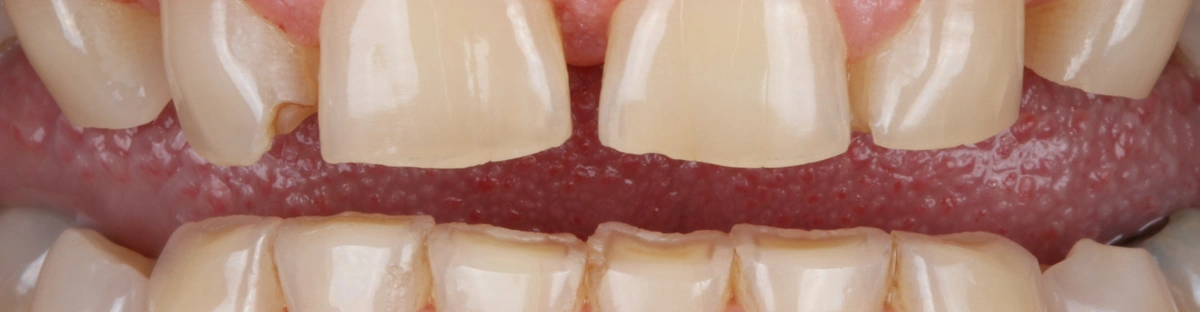

El desgaste dental se manifiesta de diferentes maneras. Puede ser leve, con signos de desgaste incipiente, que el paciente apenas percibe. Suele estar localizado en los dientes anteriores. Cuando es un poco más avanzado, se pueden observar signos y aparecer síntomas, el más común es la hipersensibilidad dentinaria. Cuando el desgaste es avanzado o severo se presenta con pérdida de esmalte y dentina con graves consecuencias para toda la dentición.

En pacientes con bruxismo excéntrico es muy frecuente la ausencia de guías caninas o ‘’colmillos planos’’ (sin cúspides), y cuando el desgaste es más avanzado, se manifiesta con una anatomía dental desgastada en molares.

Cuando el desgaste dental es leve pero hay pérdida de estructura dental, hay dos maneras de abordarlo. En caso de que sea leve pero haya pérdida de esmalte, suelo actuar con restauraciones de composite para proteger el diente y evitar que la estructura dental se siga desgastando.

Cuanto mayor es el desgaste, mayor estructura dentaria hay que reponer, por lo que el tratamiento es más complejo, no porque sea complejo de ejecutar, si no porque cuanto más desgaste, mayor número de dientes estarán involucrados en el tratamiento. El material de elección suele ser la cerámica. Son tratamientos adhesivos, en los que utilizamos la estructura dental remanente para adherirnos a ella y devolver la anatomía perdida.